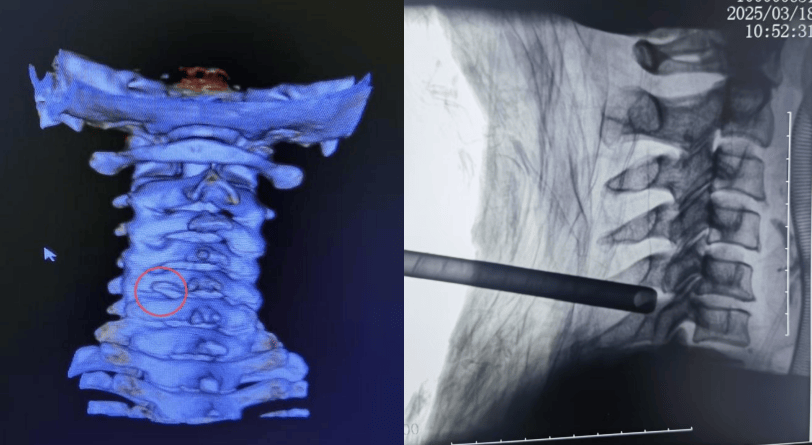

经过详细检查和评估,衢州骨伤科医院脊柱外科团队决定采用微创颈椎后路椎间孔切开术也叫Key-hole来为她进行治疗。

术中出血不到5毫升,切口长度约1厘米左右。术后患者左侧肩颈部和左上肢疼痛症状即刻得到明显缓解,经影像复查显示,保留了大部分侧块关节突关节,稳定性良好。

Key-hole即“钥匙孔”技术,指的是颈椎内镜微创手术,因为其伤口很小,在椎板上只开一个钥匙孔那么大的创口,该方法在颈部后方开约1-2cm的小孔,通过孔道去除病变髓核组织,而保留正常髓核组织。